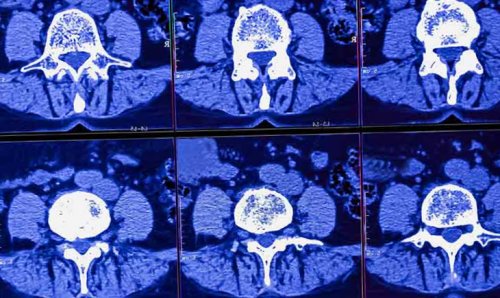

нервного корешка, считается магнитно-резонансная томография (МРТ)

или КТ пояснично-крестцового отдела позвоночника, потому что только

МРТ, КТ – позволяют четко визуализировать